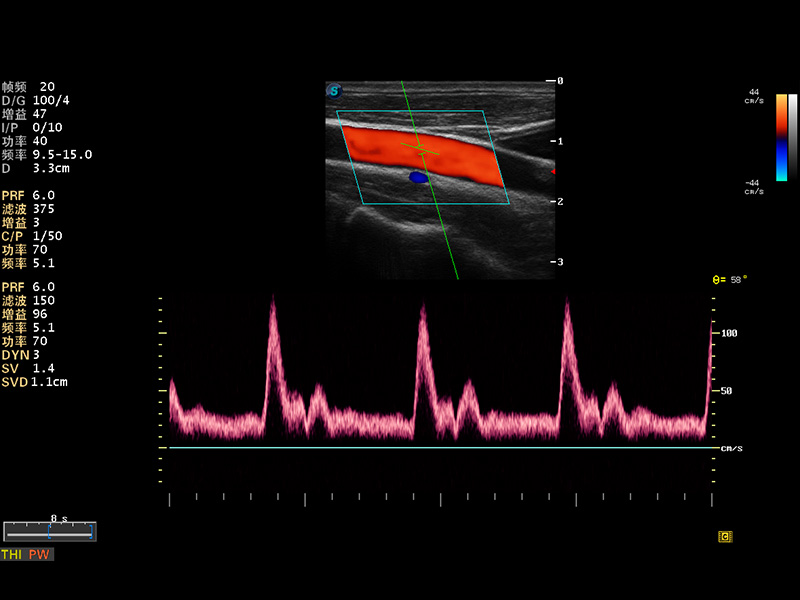

S8 EXP便携式彩色多普勒超声诊断仪是哈哈体育官网研发的高端全身应用型便携彩超。高通道的VIS平台融合可视化(Visual)、智能化(Intelligent)和人性化(Smart)的特点,配以哈哈体育官网自主研发生产的探头大家族,使您能够快速、准确的获得病人信息,提高工作效率的同时减轻疲劳。